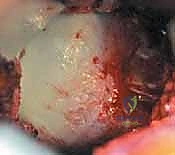

هذا الاصطدام المتكرر يشبه "المطرقة والسندان". بمرور الوقت، يؤدي هذا الاحتكاك العنيف إلى سحق أو تمزيق الشفا الحقي (Labral Tear)، وتقشير أو كشط الغضروف المفصلي الناعم من على عظم الحوض. عندما يتلف الغضروف، ينكشف العظم الأساسي، وتبدأ رحلة الألم المزمن وخشونة المفصل (Osteoarthritis).

بالإضافة إلى ذلك، تحيط بحافة التجويف الحقي حلقة قوية ومرنة من الغضروف الليفي تسمى الشفا الحقي (Acetabular Labrum). يلعب الشفا الحقي أدواراً حاسمة: فهو يعمق التجويف الحقي لزيادة الاستقرار، ويعمل كـ "سدادة" (Seal) تحافظ على السائل الزلالي داخل المفصل لتغذيته وتشحيمه، ويحتوي على نهايات عصبية تنقل إحساس الألم وتحدد موقع المفصل في الفراغ.